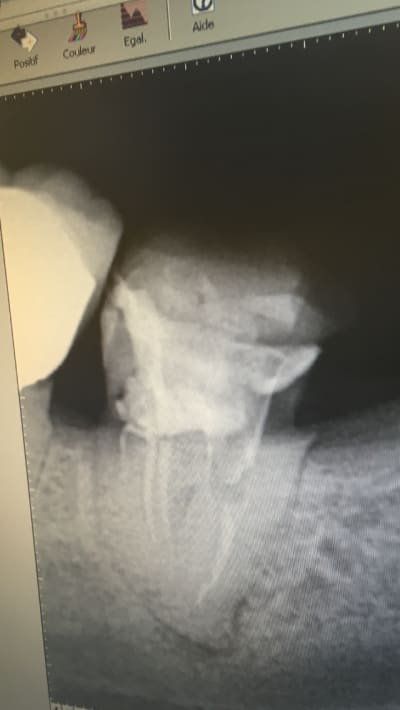

C'est rien ca, je te présente des travaux conforme aux tarifs de la grande sécurité sociale française d'un praticien qui gagne bien sa vie

Nb : le oatient venait car le bridge secteur 3 se casse la gueule : IC de 0.1 mm (sans blague), et couronne pas aux limites (qui sont de toute façon pas taillées)